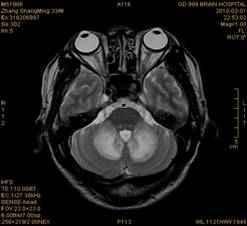

案例2 患者,女,30岁,二氯乙烷中毒性脑病的头颅MR。表现为双侧大脑半球皮层下白质、双侧外囊、双侧苍白球及双侧小脑齿状核内广泛片状、斑片状长T1长T2异常信号影,FLAIR序列呈高信号,增强后病变未见明显强化。

给予抗炎、脱水、疏通血管及营养神经等药物治疗。经过40天的对症治疗,痊愈出院。